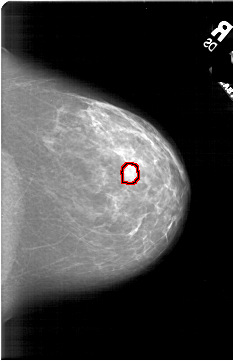

A_1813_1.LEFT_CC

LEFT_CC LINES 6241 PIXELS_PER_LINE 4441 BITS_PER_PIXEL 12 RESOLUTION 43.5 NON_OVERLAY

FILE: A_1813_1.RIGHT_CC.OVERLAY

TOTAL_ABNORMALITIES 1

ABNORMALITY 1

LESION_TYPE MASS SHAPE LOBULATED MARGINS ILL_DEFINED

ASSESSMENT 4

SUBTLETY 3

PATHOLOGY BENIGN

TOTAL_OUTLINES 1

BOUNDARY